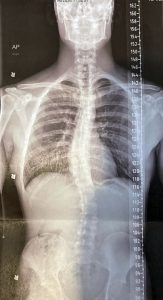

In simple terms, scoliosis is an abnormal curvature of the spine.Scoliosis is often thought of as a childhood condition, but in reality, it affects people of all ages and can look very different depending on when and why it develops.In simple terms, scoliosis is an abnormal curvature of the spine. “While the spine naturally has gentle front-to-back curves, scoliosis involves a side-to-side curve measuring more than 10 degrees. Below that threshold, it’s considered a normal variation rather than scoliosis,” explained Brigadier General John F. Hall, M.D., a board-certified, fellowship-trained orthopedic spine surgeon and owner of Arizona Precision Spine in Flagstaff. He emphasizes that not all scoliosis is the same and that understanding the type is key to understanding treatment.Congenital scoliosis, while extremely rare, is present at birth and results from vertebrae that didn’t form normally in the womb. “The building blocks of the spine are usually rectangular,” Dr. Hall said. “In congenital scoliosis, some vertebrae may be fused together or shaped more like triangles.” Juvenile idiopathic scoliosis, which occurs between ages 4 and 10, is also uncommon and is often associated with underlying medical conditions or syndromes. Because of various complexities, both congenital and juvenile scoliosis are typically treated at specialized children’s hospitals.The most familiar form is adolescent idiopathic scoliosis (AIS), which develops between ages 10 and 18. “Idiopathic means we don’t know the exact cause,” Dr. Hall explained. “If a teenager with AIS has back pain, it’s usually unrelated to the scoliosis itself.”And while it’s not hereditary, it does have a genetic component. “It is a multifactorial, familial condition, where genetic previous disposition combined with other factors increases the risk of AIS.” He says roughly 30% of cases have a family history.AIS is often detected during routine checkups. Pediatricians frequently screen for it by observing the patient’s posture or using the forward-bend test, in which children are asked to bend over and reach for their toes. Otherwise, AIS can be easy to miss.“Because it’s not painful, kids usually don’t notice it and parents may not see obvious signs until the curve has progressed.”If diagnosed with AIS, depending on the degree of the curve, wearing a specially fitted brace can help prevent curves from worsening. But, Dr. Hall notes, once someone is skeletally mature, bracing no longer works.“There’s no scientific evidence that supplements, physical therapy or alternative treatments change the curve magnitude,” Dr. Hall said. “The only things that do are bracing during growth and surgery, with surgery being the very last option.”What most people might not understand is that there is still a risk of developing scoliosis later in life, even if you don’t have AIS. The most common form of scoliosis overall is adult degenerative scoliosis, which typically develops after age 50 and is associated with disc degeneration and arthritis in the spine. Unlike scoliosis in younger years, this type is known to be painful and is usually signaled by axial back pain, or pain along the midline of the spine. Some people may also experience nerve pain that radiates down the leg, known as sciatica. There is a possibility of degenerative scoliosis getting worse with age.“The nature of degenerative conditions is that they continue to degenerate,” Dr. Hall said. “However, that’s not the same thing as saying someone will feel worse over time. There is not a one-to-one correlation between spine conditions and pain.”He explained physical therapy is the cornerstone of non-operative treatment for axial back pain. Pain-management options such as medial branch blocks, radiofrequency ablation and in some cases, spinal cord stimulation may also help. For patients with sciatica, oral anti-inflammatory medications and epidural injections are often first-line treatments.Curves that progress beyond 45 to 60 degrees, whether in adolescents or adults, are likely to continue worsening because of biomechanics alone. In those cases, surgical intervention may be necessary even if symptoms are mild. If surgery is necessary, Dr. Hall said technology has greatly transformed outcomes.“People don’t have to live the way they used to. Modern spine surgery increasingly relies on computer navigation, which allows surgeons to place screws and rods with exceptional precision using real-time 3D imaging. This technology has shown dramatic improvements in safety and effectiveness for complex scoliosis cases.”Dr. Hall emphasized that from kids to older adults, scoliosis care is never one-size-fits-all. The key is understanding the type, the risks and the right treatment at the right time. FBNBy Mary Marini Parra, FBNShare this… Facebook Pinterest Twitter Linkedin Whatsapp Post navigationWesterly sets up a business registry | Daily-news-alerts Trump Accounts: List of Companies and Individuals Providing Contributions for Children